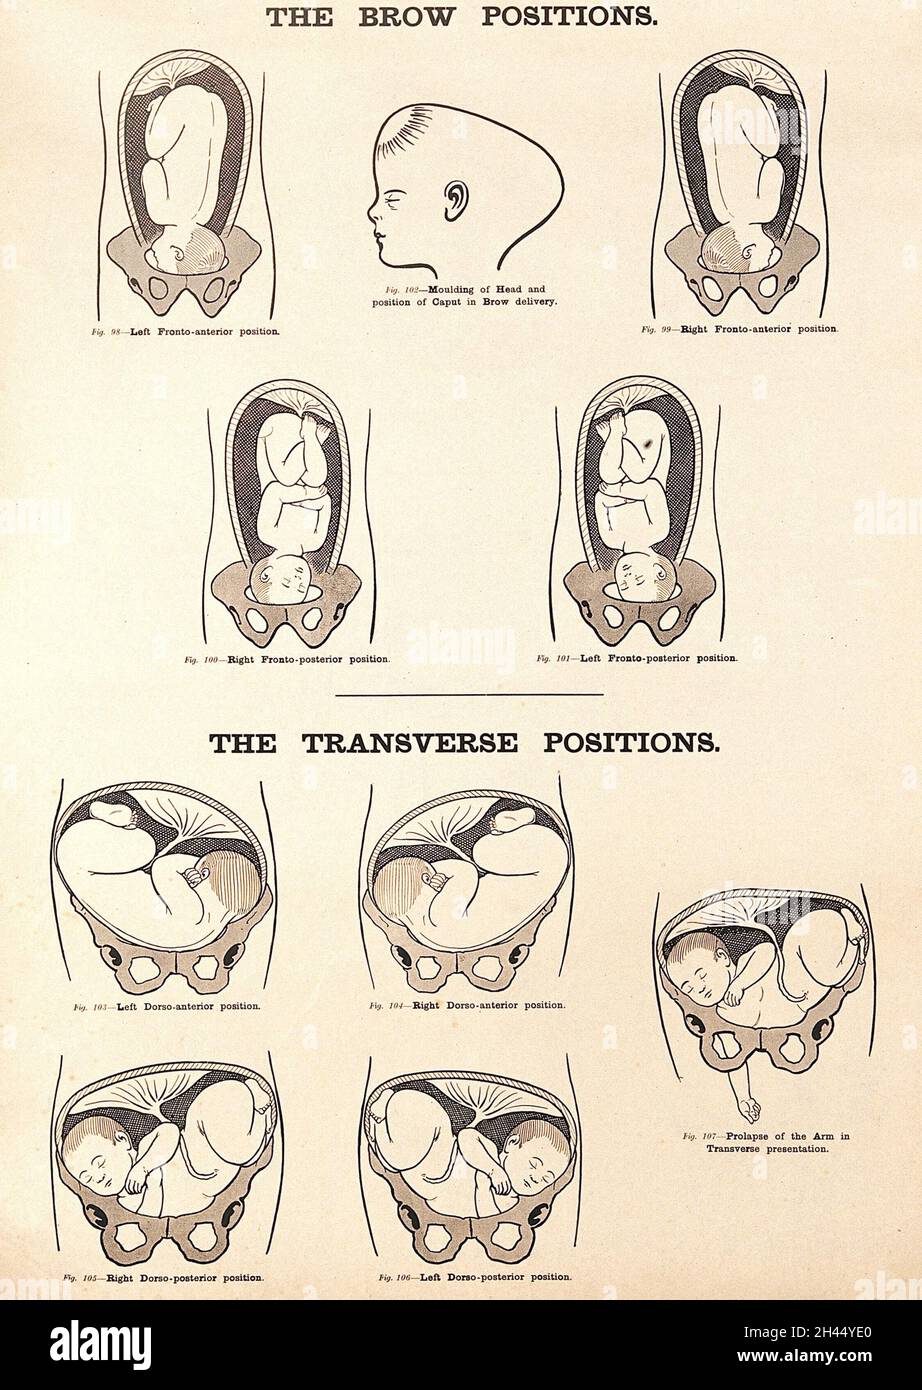

The brow positions and the transverse positions in childbirth. Lithograph after W. F. Victor Bonney. Stock Photohttps://www.alamy.com/image-license-details/?v=1https://www.alamy.com/the-brow-positions-and-the-transverse-positions-in-childbirth-lithograph-after-w-f-victor-bonney-image450037560.html

The brow positions and the transverse positions in childbirth. Lithograph after W. F. Victor Bonney. Stock Photohttps://www.alamy.com/image-license-details/?v=1https://www.alamy.com/the-brow-positions-and-the-transverse-positions-in-childbirth-lithograph-after-w-f-victor-bonney-image450037560.htmlRM2H44YE0–The brow positions and the transverse positions in childbirth. Lithograph after W. F. Victor Bonney.